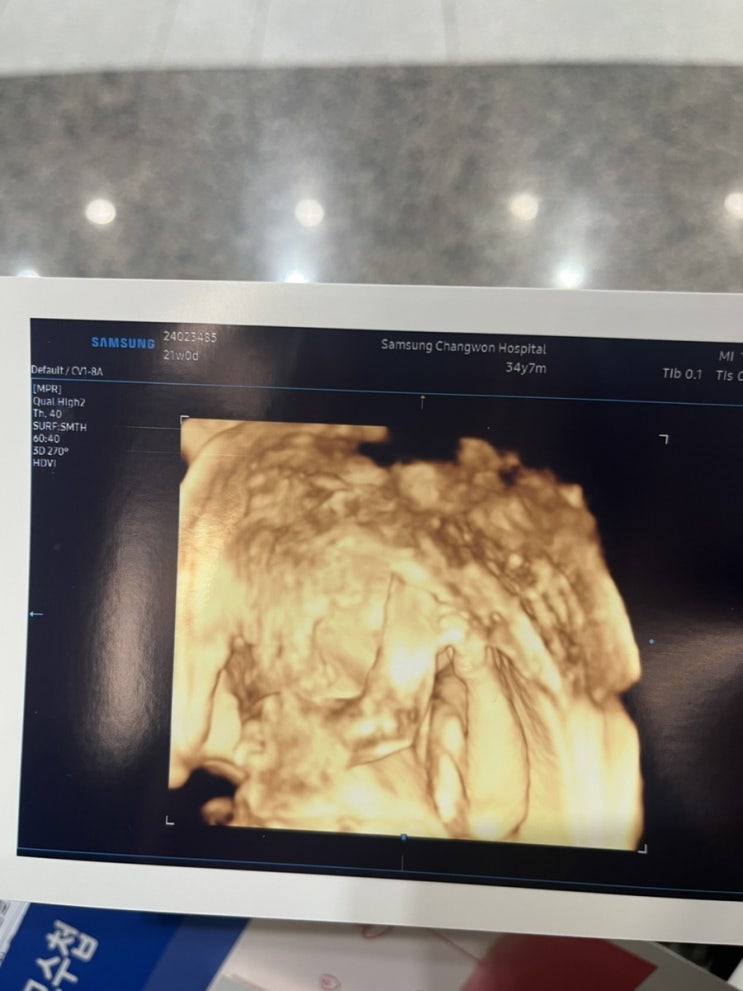

[임신일기] 21-23주! 24주 시작과 임당검사…재검확정…빠지직…

우와…나 벌써 24주차 산모가 되었다. 처음만큼은 아니지만 그래도 계속 걱정하고 또 불안해하는 바보엄마 ...

[18주-21주차] 임신일기!

우와 벌써 22주차 마미가 되었다! 지난 18-21주차 일기 더 밀리기 전에 써봐야징 주수원피스 살까말까 한참...